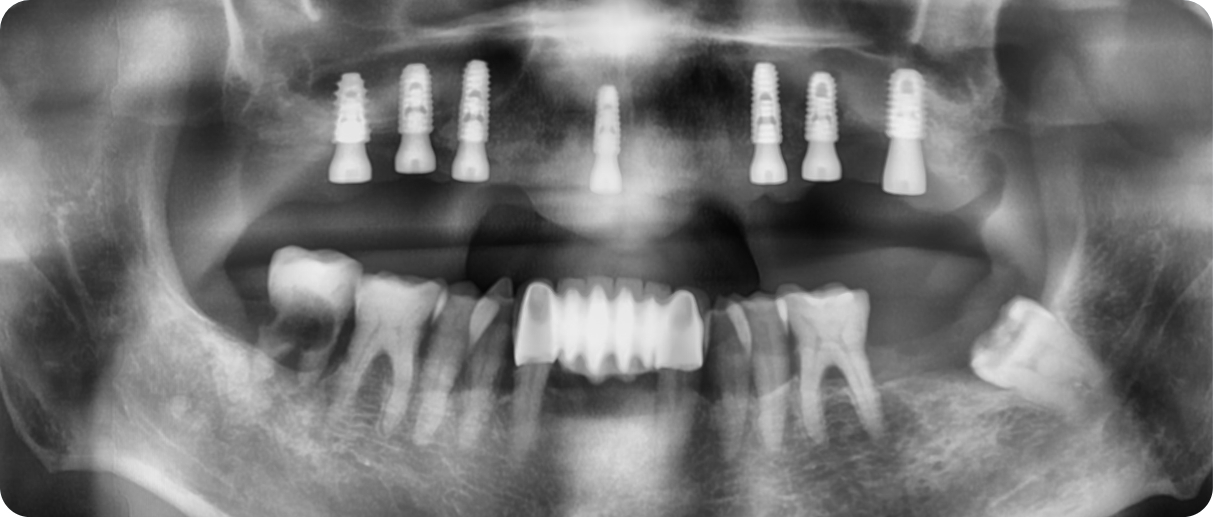

[ 이기춘님 치료 정보 ]

임플란트 식립 개수

상악 7개, 하악 전치 크라운

최종 치료 전후사진

뼈이식 정보

뼈이식 없음

임플란트 픽스쳐(기둥) - OSSTEM(오스템) BA

임플란트 MUA - OSSTEM(오스템)

최종치아 - 말로 브릿지 일체형 보철물 (탈부착 가능)